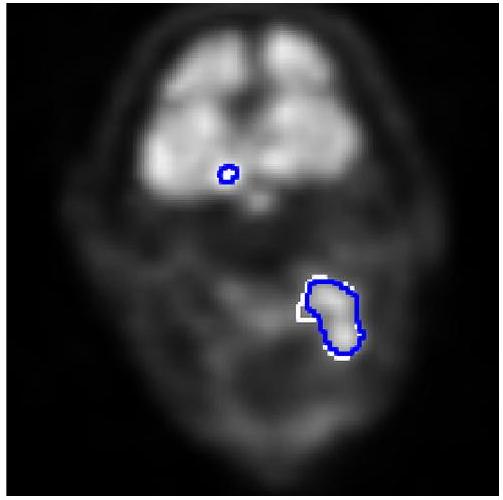

The results of the binary classification task are presented in a contingency table (Table 3) and evaluation metrics (Table 4). McNemar’s test indicates that the modified U-Net achieved significantly higher sensitivity for COVID-19 patients (p < 5.07e-5) but lower specificity for negative patients (p < 0.0207). The ROC curves for both the modified U-Net and InceptionV3, shown in Fig. 1, reveal no significant difference in their area under the curve (AUC) values (p = 0.137) according to the DeLong test. In the multi-class classification task, the modified U-Net outperformed InceptionV3 across all metrics, as confirmed by t-tests and Wilcoxon tests. The p-value for the t-test regarding the macro-average F1-score was 6.47e-4, while it was less than 2.38e-5 for other metrics. Similarly, the Wilcoxon test yielded a p-value of 0.00116 for the macro-average F1-score and less than 6.37e-5 for the remaining metrics. For the segmentation task, median and standard deviation values for Dice and Intersection over Union (IoU) metrics are provided in Table 6. Statistical tests indicate that neither Dice nor IoU values are normally distributed, with the deeper U-Net demonstrating significantly better performance in both metrics. Although the deeper U-Net exhibited a higher standard deviation, this difference was only significant for IoU values according to Levene's test.